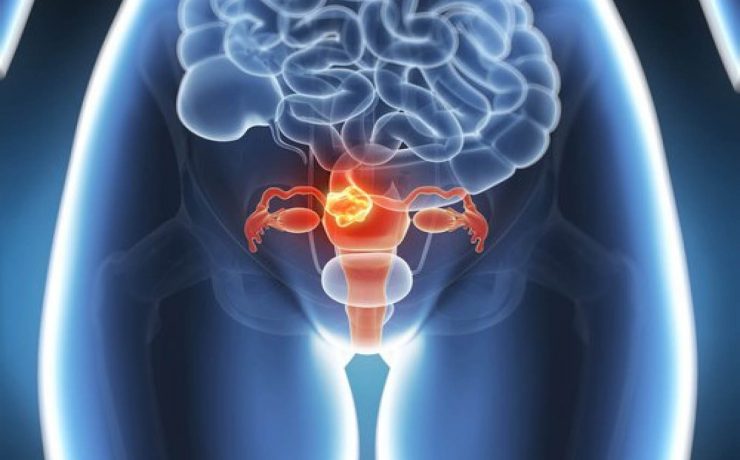

Valoración ecográfica de la patología ovárica

Existen alteraciones ováricas valorables por ecografía tratándose generalmente de alteraciones foliculares las cuales se presentan clínicamente como defectos en la maduración además del número de los mismos. Ecográficamente se diferencia el tamaño, el grosor capsular y su estroma puede estar aumentado e hiperecogénico. Otra patología son los quistes que